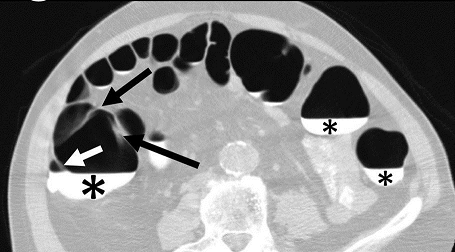

A single reviewer evaluated all data sets using a DICOM image viewer (OsiriX v4.0) for inclusion into this study. Inclusion criteria were: (1) adequate colonic distension and (2) presence of measurable folds. Having a minimum of at least five consecutive measurable haustral fold pairs in a given colonic segment was established as a marker of adequate bowel distention for optimal measurement of folds. Measurable folds were defined as folds that were not obscured or distorted by retained fluid, luminal collapse, tortuosity or diverticulosis. As haustral folds meet at the teniae coli, two of the three folds were each measured with the most dependent fold excluded; the most dependent folds were most often obscured by fluid if present (Figure 1A). Measurements of fold heights were made on 2D multiplanar reformations; the imaging plane demonstrating the folds in cross-section was established for optimal measurement of fold heights (Figure 1B). Due to the high frequency of tortuosity, suboptimal distention relative to other colonic segments, distortion of the folds and diverticulosis relative to other colonic segments, the sigmoid colon was not included in this study.

Figure 1A.Axial CT-Colonography image demonstrating dependent fluid tagging (*) obscuring a dependent haustral fold (white arrow) with a pair of unobscured, non-dependent haustral folds (black arrows). Note: difficulty in visualization of haustral fold pair due to slice selection in the axial plane.